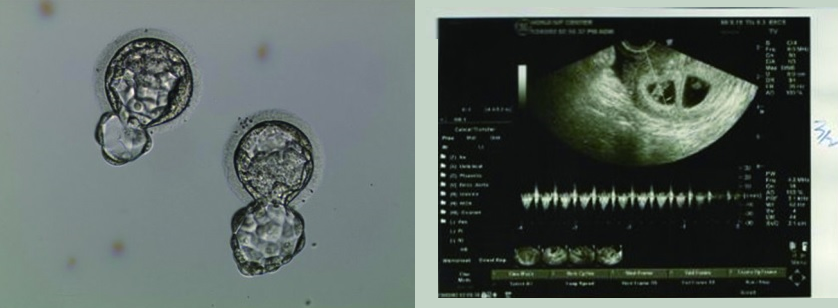

Pour la première ponction au Honji Fertility Center, on n’a eu que deux ovules et on les a déposés pendant 5 jours, l’un est devenu un embryon d’excellente qualité, l’autre est de la catégorie B; on les a vitrifiés avant de passer au deuxième traitement pour lequel on a recueilli trois ovules dont deux sont clairs et la qualité du troisième ne semblait pas meilleure que celle des deux précédents. J’ai donc décidé de faire transférer les deux premiers embryons qui ont pu nider et ont eu des palpitations. La réussite est dûe peut-être au fait que le nombre d’ovules stimulés étant moins élevé, les ovules ont pu avoir plus de nutriments et une meilleure qualité. Mais c’est aux spécialistes de trouver la bonne réponse!